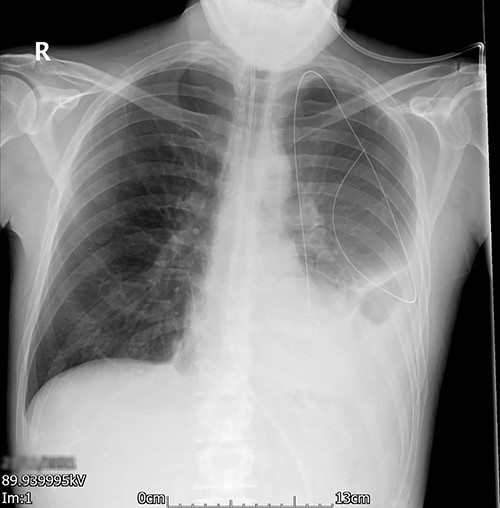

Left-sided uniportal VATS retrieval of the guidewire was done under general anesthesia (Video 1). The surgery was uneventful as was the post-operative recovery. The intercostal drain left in situ post-surgery was removed on a post-operative day (POD) 1 and the imaging done after the drain removal (Fig. 3) showed a significant decrease in pleural effusion with no guidewire in the chest cavity. He made a good recovery with an adequate physiotherapy assessment. The patient was discharged on a post-operative day (POD) 3. No follow-up was needed as he made a good recovery.

Left VATS post-operative posterior–anterior chest radiograph showing no guidewire in the left pleural cavity.